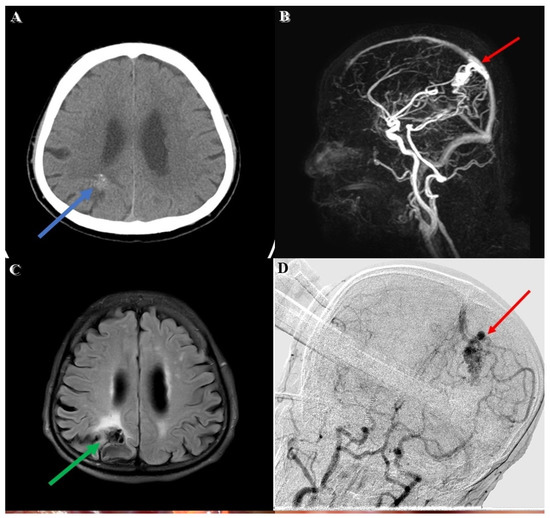

An adult patient was brought to our emergency department due to a falling accident. According to a witness, this patient suffered from a sudden change in consciousness, followed by a 3 m height fall while working. Upon arrival at our emergency department, his Glasgow Coma Scale (GCS) was E4V5M6, without any signs of specific neurological deficit. A review of his medical history showed that he had an incidental right parietal lesion with hemorrhagic vestige (Figure 1A) which was revealed through computed tomography(CT) 6 months earlier during a hospital visit for intermittent headaches. No weakness in extremities or neurological deficit was noted during this period.

Diagnostic workup involving magnetic resonance imaging (MRI) and magnetic resonance angiography (MRA) revealed a lesion with a tangle of vessels (Figure 1B) presenting itself with a signal void appearance in the right parietal region on a T2-weighted (Figure 1C) series. In addition, the Spetzler–Martin grade I AVM (size < 3 cm, superficial drainage, non-eloquent cortex) revealed evidence of a rupture with hemorrhage. The main arterial supply was comprised in the right terminal branch of the posterior cerebral artery and the parietal branch of the middle cerebral artery, with superficial drainage into cortical vein superiorly.

The first stage of the operation for the patient’s AVM resection was confirmative digital subtraction angiography (DSA) (Figure 1D) followed by right parieto-occipital craniotomy. After performing a dura opening, surgery proceeded to the microsurgical stage performed under a microscope (Figure 2A). With assistance from the AR technique, the feeding arteries from the posterior cerebral artery and the parietal branch of the middle cerebral artery were labeled with red and yellow color, respectively, and then projected onto the cortex. Furthermore, the AVM nidus was coded with blue color for identification (Figure 2B). In the next dissection and resection stage, we adjusted the focal length and hologram setting to clarify the surgical field. After confirmation of the spatial relationship in the angiographic complex, both coagulation and clipping were performed to obliterate the feeding artery (Figure 2C). After the clipping and coagulation of the first feeding artery from the middle cerebral artery, we proceeded to obliterate another feeding artery from the posterior cerebral artery (Figure 2D). Eventually, the AVM nidus got resected after both the feeding arteries were obliterated.

Figure 1. Preoperative and intraoperative images. (A) Right parietal suspected vascular lesion with hemorrhagic vestige from computed tomography (CT) (blue arrow). (B) Preoperative reconstructive magnetic resonance angiography (MRA) revealed the tangled vascular lesion (red arrow) (C) Flow voiding phenomenon was noted from T2-weighted image (green arrow). (D) Intraoperative digital subtraction angiography (DSA) for confirmation of lesion location.